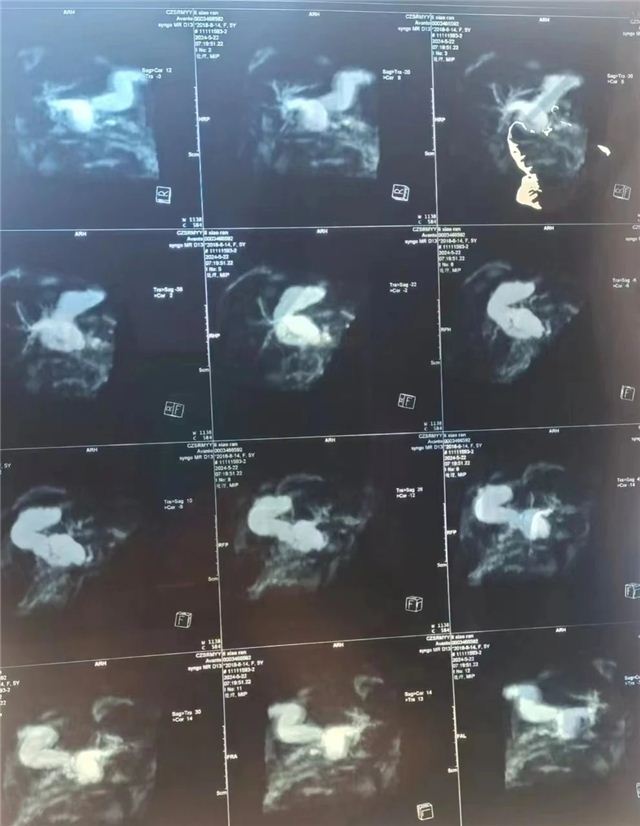

住院后经过检查,花花的胆总管囊肿已经合并感染,并且合并胰腺炎。在李现令副院长的指导下,很快感染及胰腺炎得到控制,5月27日,在麻醉科的全力配合下,在北京儿童医院黄柳明教授及李现令教授的指导下,为患儿行腹腔镜下胆总管囊肿切除+肝总管空肠Roux-Y吻合术。术后,在小儿外科护理团队精心的照护下,花花已顺利恢复。

先天性胆总管囊肿是先天性胆道发育畸形,可在产前检查时发现,有的孩子因为腹痛行彩超检查时发现。目前小儿外科治疗胆总管囊肿都是微创手术治疗,腹腔镜下胆总管囊肿切除+肝总管空肠Roux-Y吻合术是主流术式。该手术的开展也体现了长治市妇幼保健院小儿外科在山西省的技术水平。